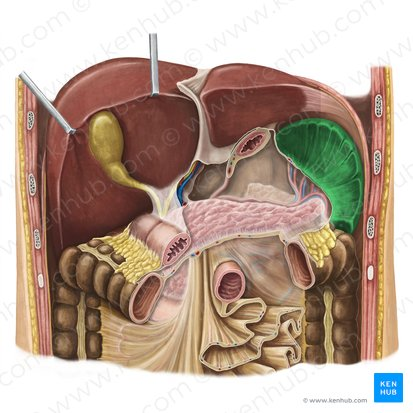

Right lobe of Liver

The larger of the two main lobes of the liver, located on the right side of the abdomen.

Left lobe of the Liver

The smaller of the two main lobes of the liver, located on the left side of the abdomen.

Quadrate Lobe

A small, quadrilateral lobe of the liver located inferiorly and medially on the visceral surface, bordered by the gallbladder and the fissure for the round ligament.

Caudate Lobe

A small lobe of the liver located posteriorly on the visceral surface, near the inferior vena cava and the fissure for the ligamentum venosum.

Falciform Ligament of the Liver

A broad, thin fold of peritoneum that attaches the liver to the anterior abdominal wall and diaphragm. It also marks the division between the right and left lobes on the anterior surface.

Round Ligament of the Liver

A fibrous cord that represents the remnant of the umbilical vein of the fetus. It is located in the free edge of the falciform ligament.

Gallbladder

A small, pear-shaped organ located beneath the liver that stores and concentrates bile produced by the liver.

Right Hepatic Duct

A duct that carries bile produced by the right lobe of the liver.

Left Hepatic Duct

A duct that carries bile produced by the left lobe of the liver.

Common Hepatic Duct

The duct formed by the union of the right and left hepatic ducts, which carries bile away from the liver.

Cystic Duct

The duct that connects the gallbladder to the common hepatic duct, allowing bile to enter and exit the gallbladder.

Hepatic Artery

A branch of the celiac artery that supplies oxygenated blood to the liver.

Hepatic Portal Vein

A large vein that carries deoxygenated but nutrient-rich blood from the digestive organs (stomach, intestines, spleen, pancreas) to the liver for processing.

Inferior Vena Cava

A large vein that carries deoxygenated blood from the lower and middle body back to the heart.

Pancreatic Duct / Duct of Wirsung

The main duct that runs through the length of the pancreas, collecting digestive enzymes from the pancreatic cells and transporting them to the duodenum.

Accessory Pancreatic Duct / Duct of Santorini

A smaller pancreatic duct that branches off the main pancreatic duct and may also empty into the duodenum, usually superior to the major duodenal papilla.

Hepatopancreatic Ampulla / Ampulla of Vater

A dilated chamber formed by the joining of the common bile duct and the pancreatic duct before they enter the duodenum.

Sphincter of Hepatopancreatic Ampulla / Sphincter of Oddi

A muscular valve that surrounds the hepatopancreatic ampulla and controls the flow of bile and pancreatic juice into the duodenum.

Major Duodenal Papilla

The raised opening in the wall of the duodenum where the hepatopancreatic ampulla typically empties its contents.

Mucosa of Duodenum

The inner lining of the duodenum, which contains specialized cells for absorption and secretion.